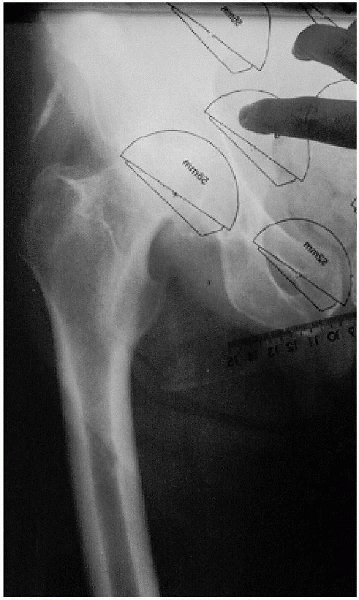

FIGURE 20-1. Leg-length determination on anteroposterior radiograph.

an anteroposterior (AP) view of the pelvis, centered low to include the

proximal half of the femur, as well as a lateral radiograph of the hip.

A line drawn tangential to the bottom of the ischial tuberosities is

used to determine the amount of preoperative leg-length discrepancy as

the difference between this line and the top of the lesser trochanter

bilaterally (Fig. 20-1). Clear overlay